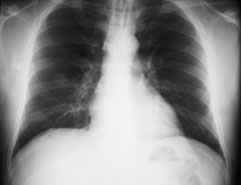

Radiologie Quiz 34

Ein 41-jähriger Mann sucht Sie auf, weil er zum dritten Mal in diesem Winter erkältet ist und dieses Mal sogar mit Fieber. Er gibt ausserdem an, etwas trockenen Husten zu haben. Ausserdem besteht seit Wochen eine Sinusitis, die nicht so recht abheilen will.

Gewichtsverlust wird verneint. Der Patient ist Nichtraucher und fühlte sich bis anhin gesund.

Die Lungenperkussion und -auskultation ist unauffällig. Das Labor zeigt eine Leukozytose ohne Linksverschiebung und ein CRP von 97 mg/dl. Hier das Röntgenbild der Lunge:

Thorax pa

Welche Befunde fallen Ihnen auf?

Es ist klar, dass aufgrund dieses Befundes keine Diagnose gestellt werden kann. Welche Diagnose ist aufgrund der Klink und des radiologischen Befundes am wahrscheinlichsten?